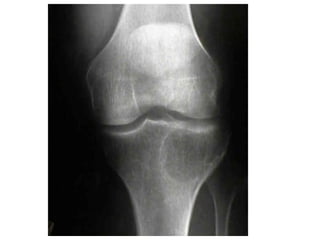

Arthritis

Gout

overload of uric acid in the body. This

Gout • Gout isa disease that results from an overload of uric acid in the body. This overload of uric acid leads to the formation of tiny crystals of urate that deposit in tissues of the body, especially the joints. When crystals form in the joints it causes recurring attacks of joint inflammation (arthritis). Chronic gout can also lead to deposits of hard lumps of uric acid in and around the joints and may cause joint destruction, decreased kidney function, and kidney stones.